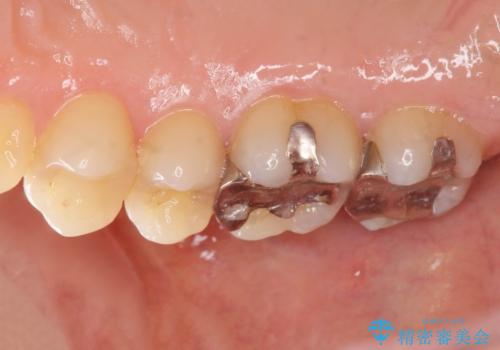

メタルフリー治療 銀歯を全て除去したい

- 口腔内の金属、銀歯を全て除去しセラミックにしたい。と、希望され来院されました。

口腔内の金属を丁寧に除去したのち、精度・審美性に優れるセラミック治療を計画します。